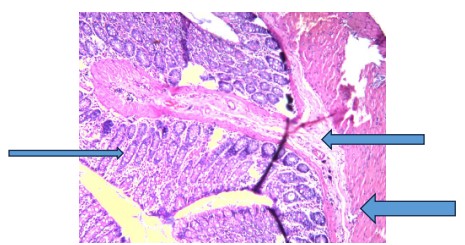

Sections of the colon tissues of rats exposed to 1,2-dimethylhydrazine revealed inflamed colon mucosa and tumor development in the colon when compared with control, which displayed normal mucosa (very thin arrow) consisting of columnar epithelium, lamina propria, and muscularis mucosa (Fig. 1). Also, the underlying submucosa (thin arrow) and muscularis propria (thick arrow) are essentially normal.

The irregularities detected in the DMH group, as shown in Fig. 2, are due to increased cell proliferation, apoptosis, and the formation of preneoplastic lesions and tumors18. Consequently, segments of colon tissues of rats administered V. amygdalina alone or before and after DMH induction revealed mild to moderate recovery from early signs of colon tumorigenesis, followed by reduced inflammatory cell infiltration as shown in Fig. 3-8, respectively. This suggests that the extract can improve colon histoarchitecture deformities because of its protective effects, which are characterized by bioactive components like flavonoids, saponins, and polyphenols present in it19.